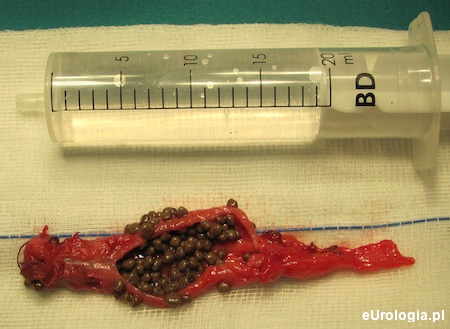

Pęcherz zszyto dwuwarstwowym wchłanialnym szwem ciągłym z pozostawieniem drenu cystostomijnego 14 Ch. W rozciętym kikucie moczowodu uwidoczniono kilkadziesiąt złogów koloru oliwkowego o średnicy 1–3 mm (ryc. 3, 4). W wyniku histopatologicznym wyciętego kikuta stwierdzono Inflammatio chronica erosiva cum calcificationibus in pariete (hist. pat. 4433-34/10).

Ryc. 3 Usunięty kikut moczowodu

Ryc. 4 Liczne złogi w rozciętym kikucie moczowodu